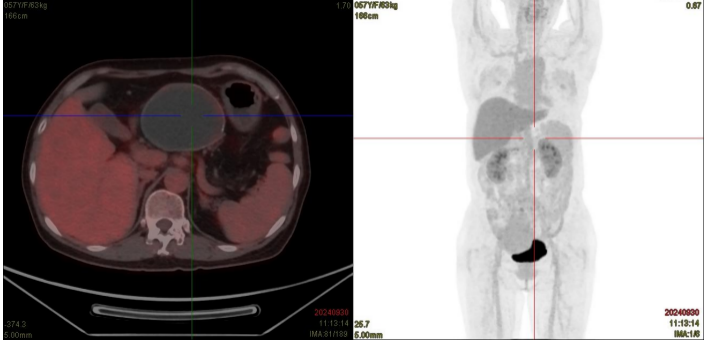

患者为57岁女性,因“发现肝门部占位4月余”来院就诊,住院后完善增强CT、MR检查后考虑肝门部占位为胰头来源肿瘤,囊腺瘤可能,病灶内局部壁结节形成,未排恶变可能,胆总管下段、门静脉、下腔静脉、十二指肠均明显受压。

CT示肝门部肿物,大小约4cm×7cm,位于门静脉及下腔静脉间隙,门静脉、下腔静脉受压。